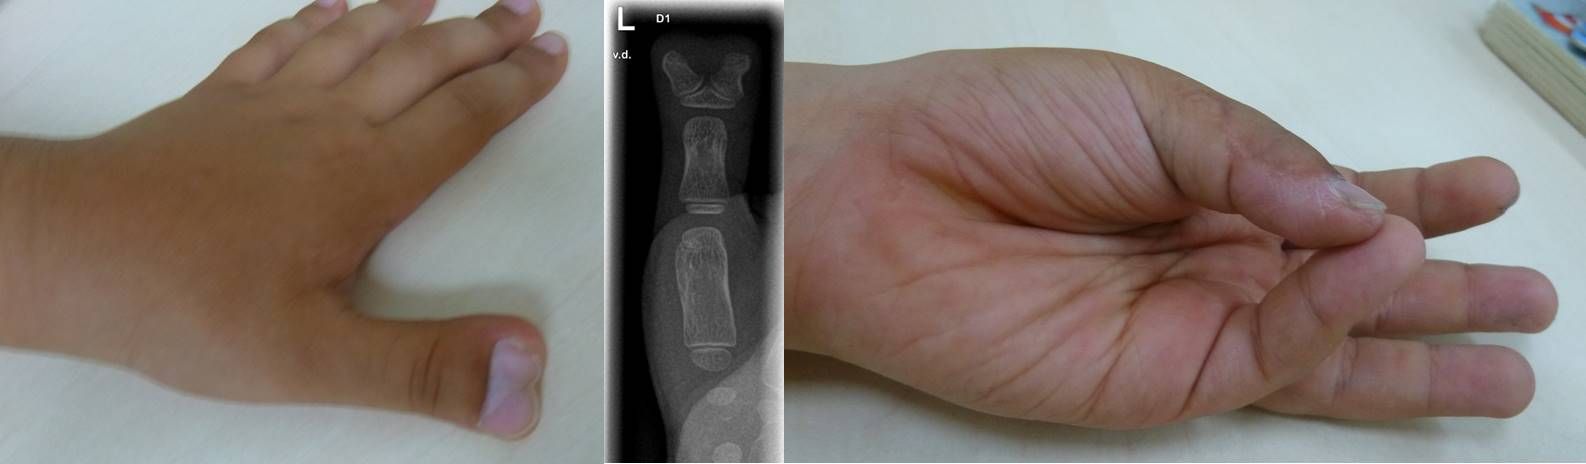

Die Einteilung erfolgt nach Lokalisation - radial, auf der Seite des Daumens - Zentral, im Bereich von Zeige-, Mittel- oder Ringfinger - ulnar, auf der Seite des Kleinfingers.

Die einfachste Form besteht in einer rudimentären Anlage des gedoppelten Fingers als kleines  Anhängsel, dessen operative Entfernung unkompliziert ist und ab dem 3. Lebensmonat ambulant durchgeführt werden kann.

Bei der kompletten Doppelung ganzer Finger, erfolgt die operative Korrektur meist erst nach dem ersten Geburtstag. Das klinische Bild kann dabei, je nachdem, auf welcher Höhe sich der Daumen in zwei Anlagen aufteilt, sehr unterschiedlich sein. Die Korrektur besteht dabei nicht im einfachen Entfernen der überzähligen Anteile. Die oft anspruchsvolle Operation umfasst die Korrektur der meist zusätzlich bestehenden Verschmelzung von knöchernen gedoppelten Anteilen sowie die Stabilisierung des Bandapparates der betroffenen Gelenke und Verlagerung von Muskelansätzen des Daumenballens. In manchen Fällen muss auch eine Korrektur der knöchernen Achse erfolgen. Die Begrifflichkeit „Doppeldaumen“ ist hier manchmal irreführend, da es sich nicht um zwei normal entwickelte Daumen handelt sondern um Anteile eines Daumens, die sich auf zwei Anlage verteilen; somit ist der verbleibende Daumen fast nie so kräftig wie der gesunde Daumen der Gegenseite.